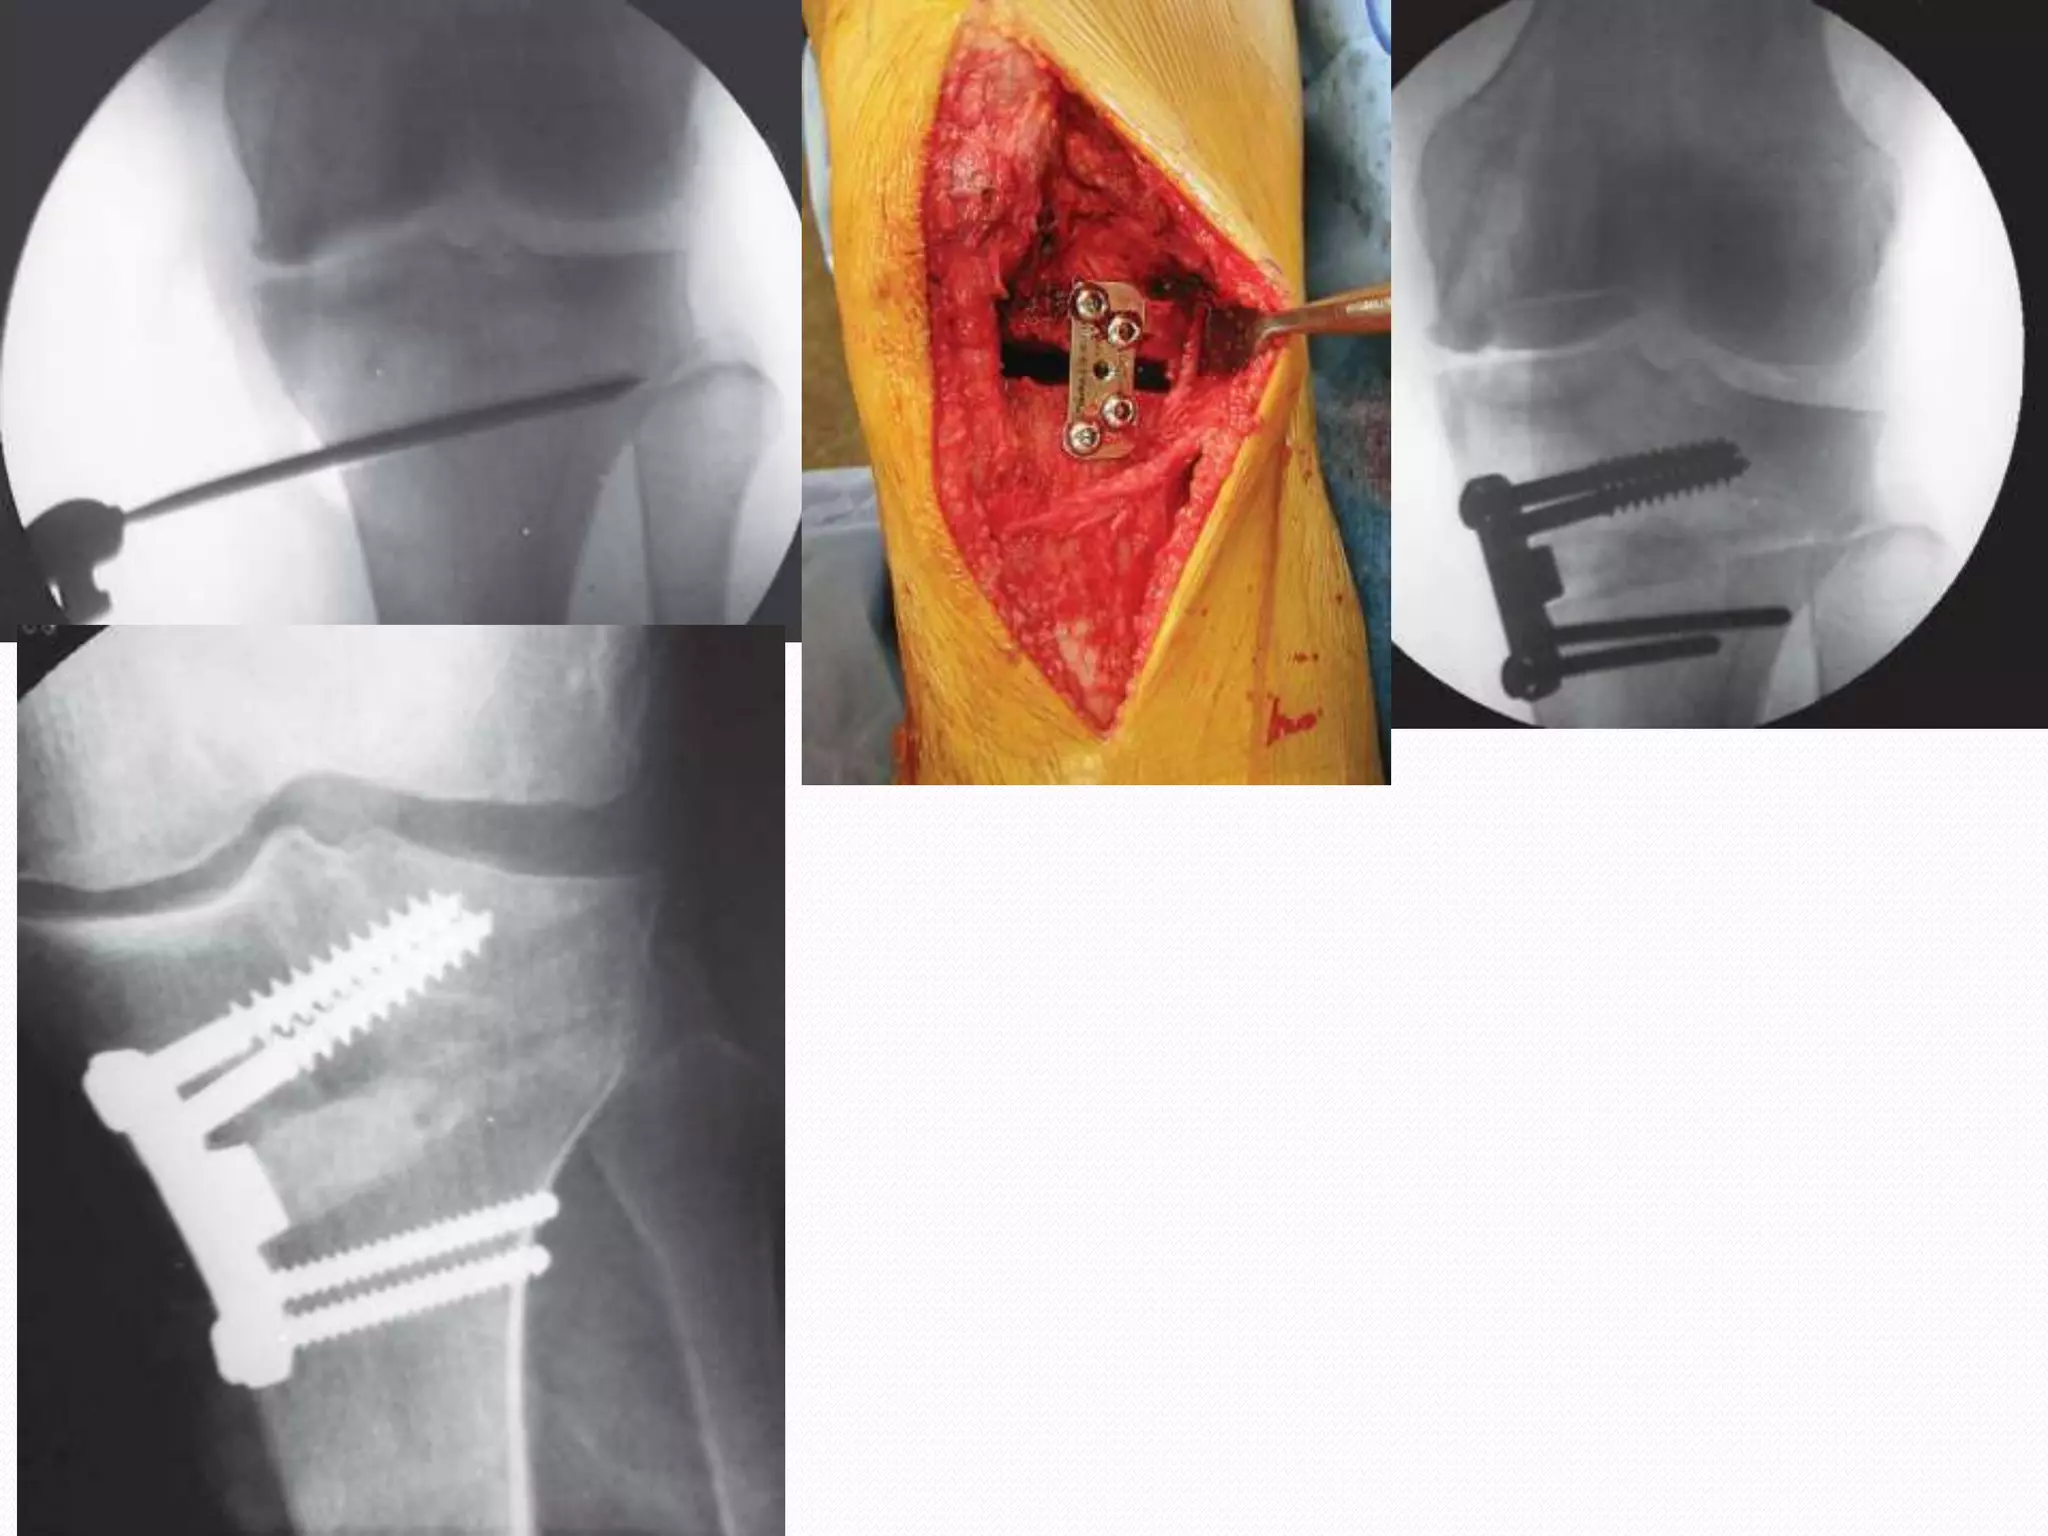

Tomofix plate

Puddu-chambat plates

Staples

LRS and ilizarov

Pros  Most stable Early consolidation  Early mobilisation  Exploration of knee joint through same approach Cons  Limb shortening  Nerve injury  LCL laxity  Patella Baja

Advantages  Usual deformityis proximal tibia vara, which is addressed directly  Preservation of bone at proximal tibia  No disruption of proximal tibio fibular joint or anterior compartment  Less chances of nerve injury  Correction can be modified intra-operatively

Disadvantages  Non-union  Longertime to consolidation  Longer duration of immobilisation  Donor site morbidity  Limb lengthning  Shifts tibial tubercle laterally  Patello-femoral symptoms